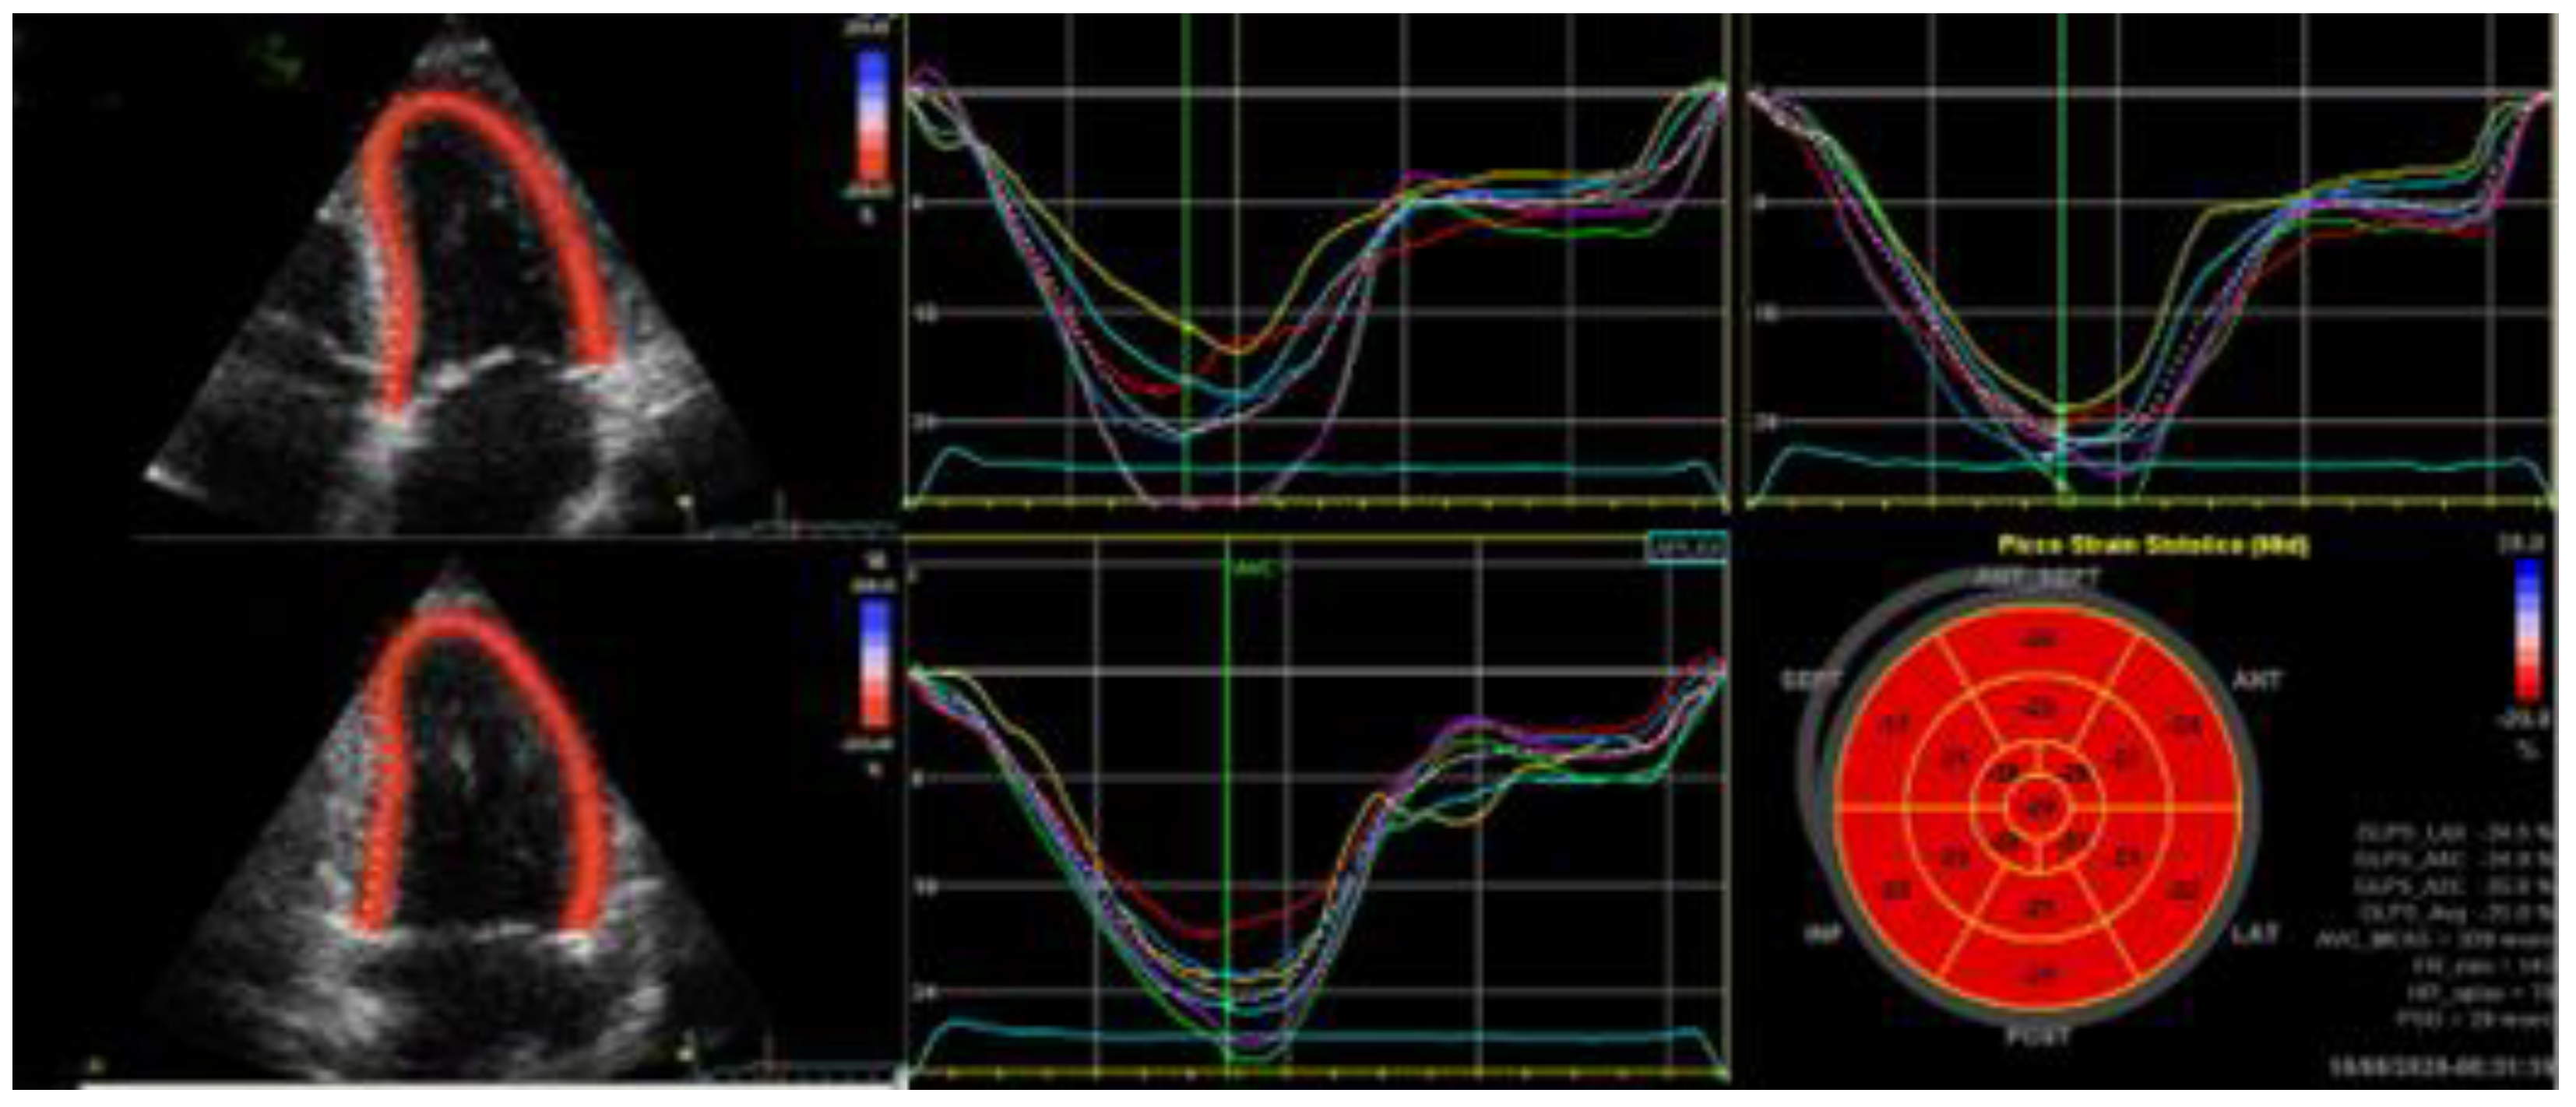

2. Global Longitudinal Strain

2.1.1. HFrEF